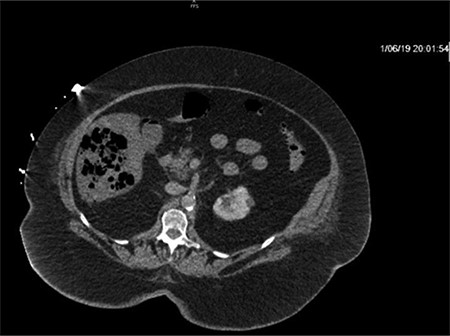

CT of the abdomen and pelvis with IV contrast was performed within 2 h of presentation. The scan showed “indeterminate, scattered ill-defined hypo-enhancing lesions in the liver with no acute etiology identified to explain the patient’s abdominal pain” (Figs 1, 3, 5). The remainder of the CT was unremarkable. Ultrasound (US) of the abdomen was negative. Because the CT and US did not identify an etiology for the patient’s abdominal pain, the working diagnosis at that time was an intestinal obstructive process.

CT with IV contrast taken at 0633 which shows ill defined, hypo-enhanced lesions of the liver.